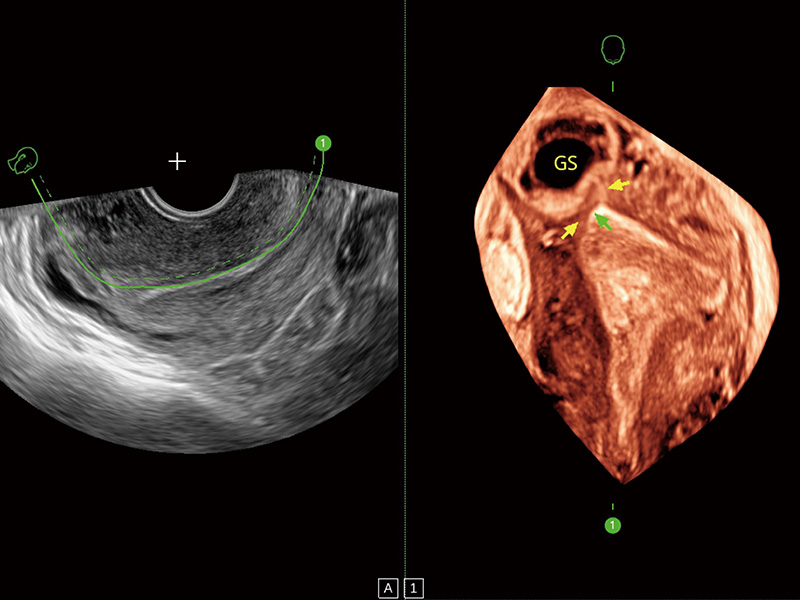

“生育问题”即关系民族复兴,也关系亿万家庭的幸福。随着婚育年龄推迟、社会压力增加等因素,越来越多人群也面临着“生不出、生不好”的问题。辅助生殖作为治疗不孕不育最有效的方法之一,也逐渐成为育儿新希望。而超声检查能为生殖需求人群的初诊评估提供宝贵的信息。 P20 Elite是新葡的京集团8814检测站匠心打造的一款生殖应用型彩超。她继承新葡的京集团8814检测站高端极光平台,突破性地将多款新型芯片及硬件模块进行整合,均衡了高端系统性能与小巧灵动机身。P20 Elite卓越的图像质量搭载专科探头,旨在为您提供全面的辅助生殖解决方案。

P20 Elite配备了丰富的生殖探头群和临床应用功能,在卵泡监测、穿刺取卵、胚胎移植、妊娠确认等领域,为生殖需求人群提供了新的临床机会,重新定义高端超声如何应用于生殖健康检查。